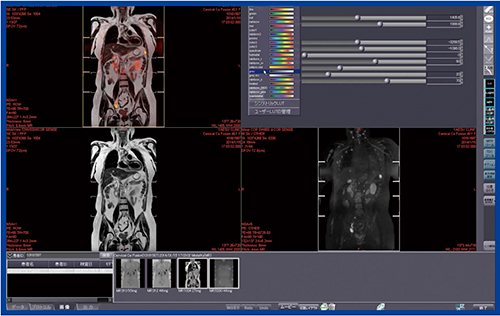

Ziostation2のMR/MRフュージョンでは,2DのT1WIを表示してフュージョンのレイアウトを立ち上げ,DWIを所定の位置にドラッグ&ドロップするだけでフュージョン画像が容易に作成可能であり,Windowや色味の調整,シネ画像の作成も簡単に行うことができる(図1)。また,スムーズな閾値設定のために非常に重要なAlpha/Blendパラメータが,スライダーバーで容易に変更可能である。

図1 MR/MRフュージョン